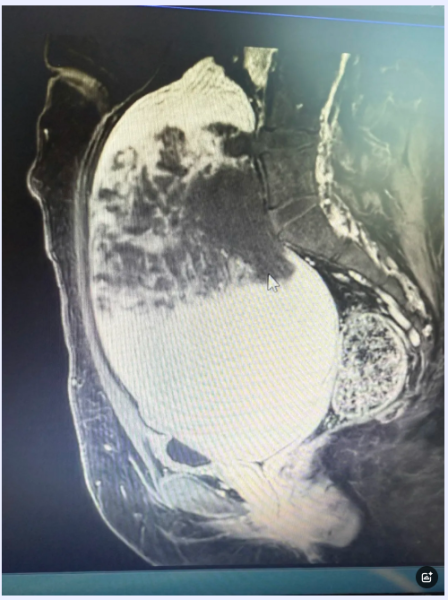

患者自述于一年前自觉下腹触及包块,最近一段时间内,在她平躺状态下,腹内肿物已明显高于腹壁,且伴有尿频症状,“能否保住患者的子宫”是摆在胡主任面前的一大困难。在接下来的术前检查中,发现小丽还患有先心病及左肾占位性病变伴有蛋白尿,超声报告显示:盆腔肿物大小230mm*125mm*175mm,与肌层边界不清。经多科室会诊(心内科、麻醉科、影像科、泌尿外科及输血科),再看到患者渴望的眼神,胡主任有底气与这个“庞然大物”进行较量。

手术当日,胡主任医疗团队在全麻下对大肿物进行了全面探查,虽有充分准备还是被眼前的肌瘤震惊,打开腹腔肉眼所见皆是肌瘤,肌瘤占据了整个盆腔及中腹部,表面血运极其丰富。凭借丰富的手术经验,胡春杰教授团队游刃有余的完整切下了瘤体。术后第二日,小丽已能下地行走,看到腹壁远小于瘤体的切口,以及得知自己还可以正常生育,她对胡春杰主任的感激之情一语难表!